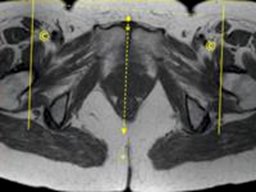

AX OBL PD (TE=20msec) TSE 3-4 mm 0.5-1mm None 20cm Parallel anterior iliac crest, from crest thru hip joint

AX OBL T2 SPAIR TSE 3-4 mm 0.5-1mm SPAIR 20cm Parallel anterior iliac crest, from crest thru hip joint

MRI Pelvis Sports Hernia WO MSK Protocol image 2